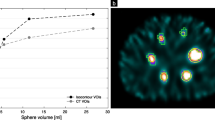

Kidney and lesion SUV

In Fig. 2, the correlation plots for the SUV for 440 keV (213Bi) and 218 keV (221Fr) at 24 and 48 h p.i. are shown for a total of eight kidneys and nine lesions. The left kidney of patients 3 and 5 were excluded from the analysis due to high intestinal uptake at 48 h p.i., which superimposed onto the left kidney. The SUVs show a very strong correlation for both time points and in both, the lesions (24 h, r = 0.93, p-value = 0.0006; 48 h, r = 0.96, p-value < 0.0001) and the kidneys (24 h, r = 0.94, p-value = 0.0004; 48 h, r = 0.99, p-value < 0.0001). Figure 3 shows the kidney and lesion SUV for all three peaks (440 keV, 218 keV, and 78 keV) at 24 and 48 h post-treatment. Further details on the SUV per energy window and time point are found in Table 2. In addition, Table 3 shows the corresponding SUV ratios at 24 and 48 h post-treatment.